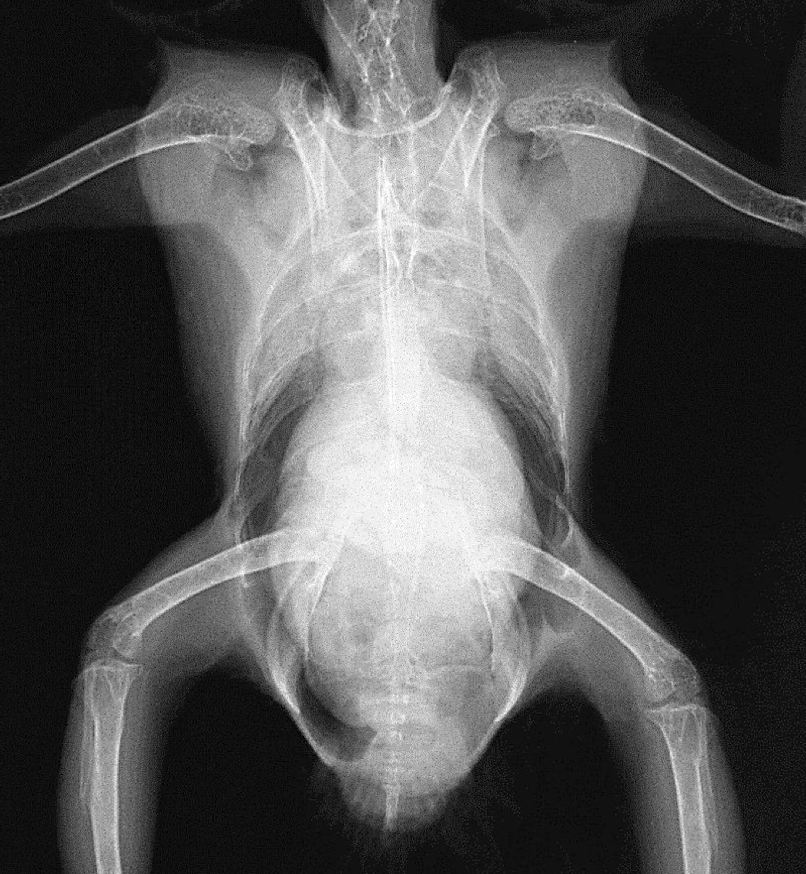

What is the normal heart width on a VD radiograph for psittacines and hawks?

Less than 60% of the thoracic width.

Great vessels in the heart VD

Great vessels in the heart lateral